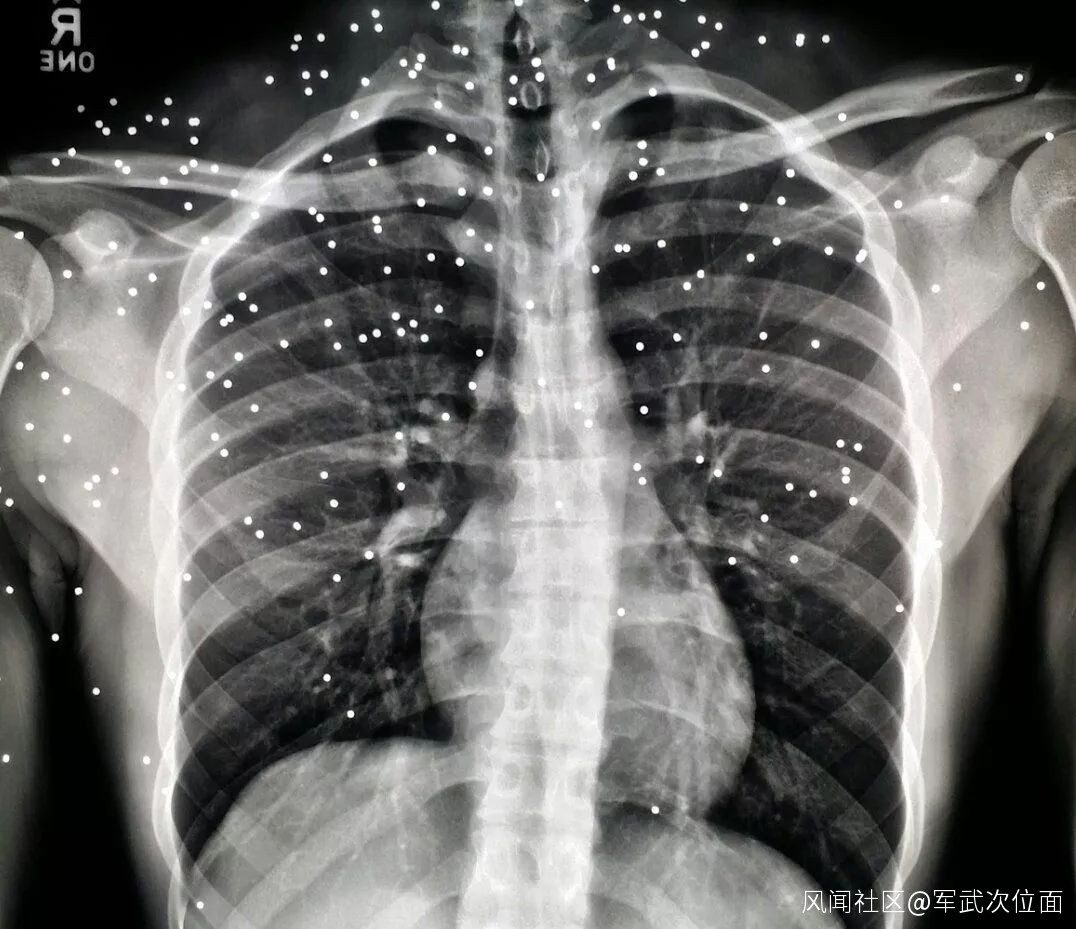

▲血腥圖就算了,給大家看看被鳥彈擊中後的X光照片

這裏有一張鳥彈射擊人體凝膠的照片。注意鳥彈的侵徹深度,子彈在彈道凝膠中的侵徹深度大約是真實人體中的兩倍,所以最壞的情況,在有效距離內,鳥彈的侵徹深度也很難超過7cm深,如果射擊距離較遠,一個人穿的衣服比較厚,而子彈又沒有擊中要害的情況下,生還幾率還是較大的。

當然,劇痛和慘不忍睹的皮外傷是跑不了的。有網友曾爆料説自己在5米距離被鳥彈從背後意外擊中,當時的感受就像是被人猛推了一下,開始並沒有疼痛的感覺,但是隨後發現背上嵌入無數的鋼珠,簡直是酸爽無比。